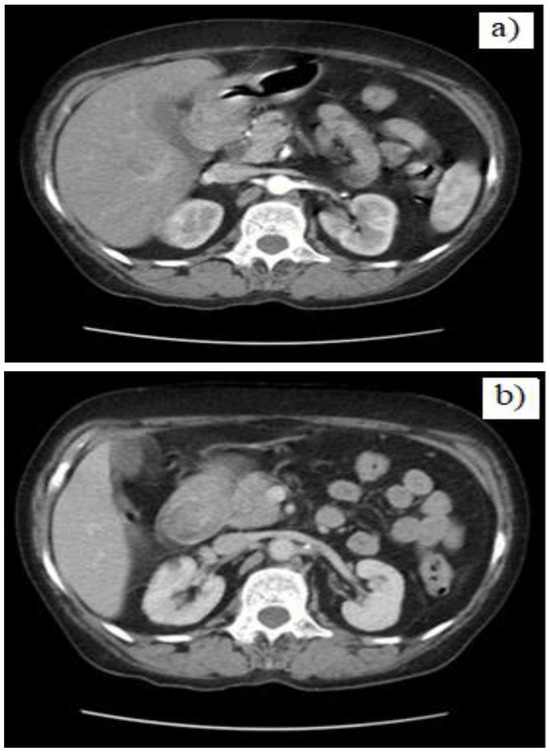

Case presentation